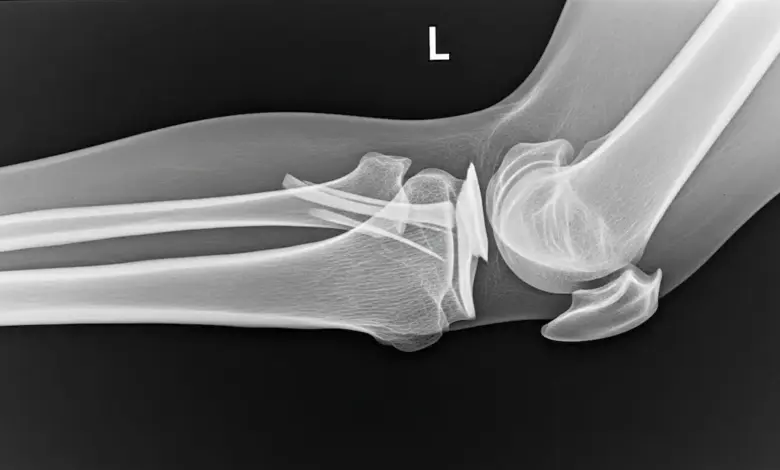

A radiografia é o primeiro passo. Ela pode mostrar a fratura por avulsão e já levantar a suspeita com rapidez.

A tomografia ajuda bastante quando é preciso avaliar melhor o tamanho do fragmento, sua posição e o grau de deslocamento.

Já a ressonância magnética é útil para olhar menisco, cartilagem, edema ósseo e outras estruturas ligamentares.